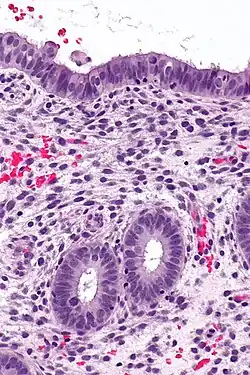

![]() |

Lepromatous leprosy | Skin biopsy showing epidermal atrophy and multiple dermal infiltrates. | Category: Histopathology of leprosy | Leprosy |